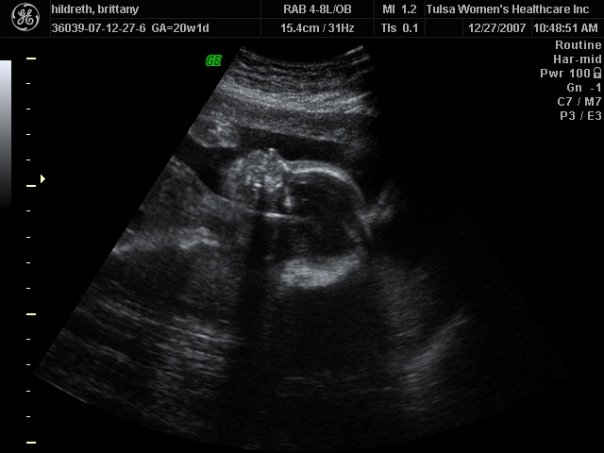

| Loved that little round head! 20 weeks- the day she found out we were having a GIRL! |